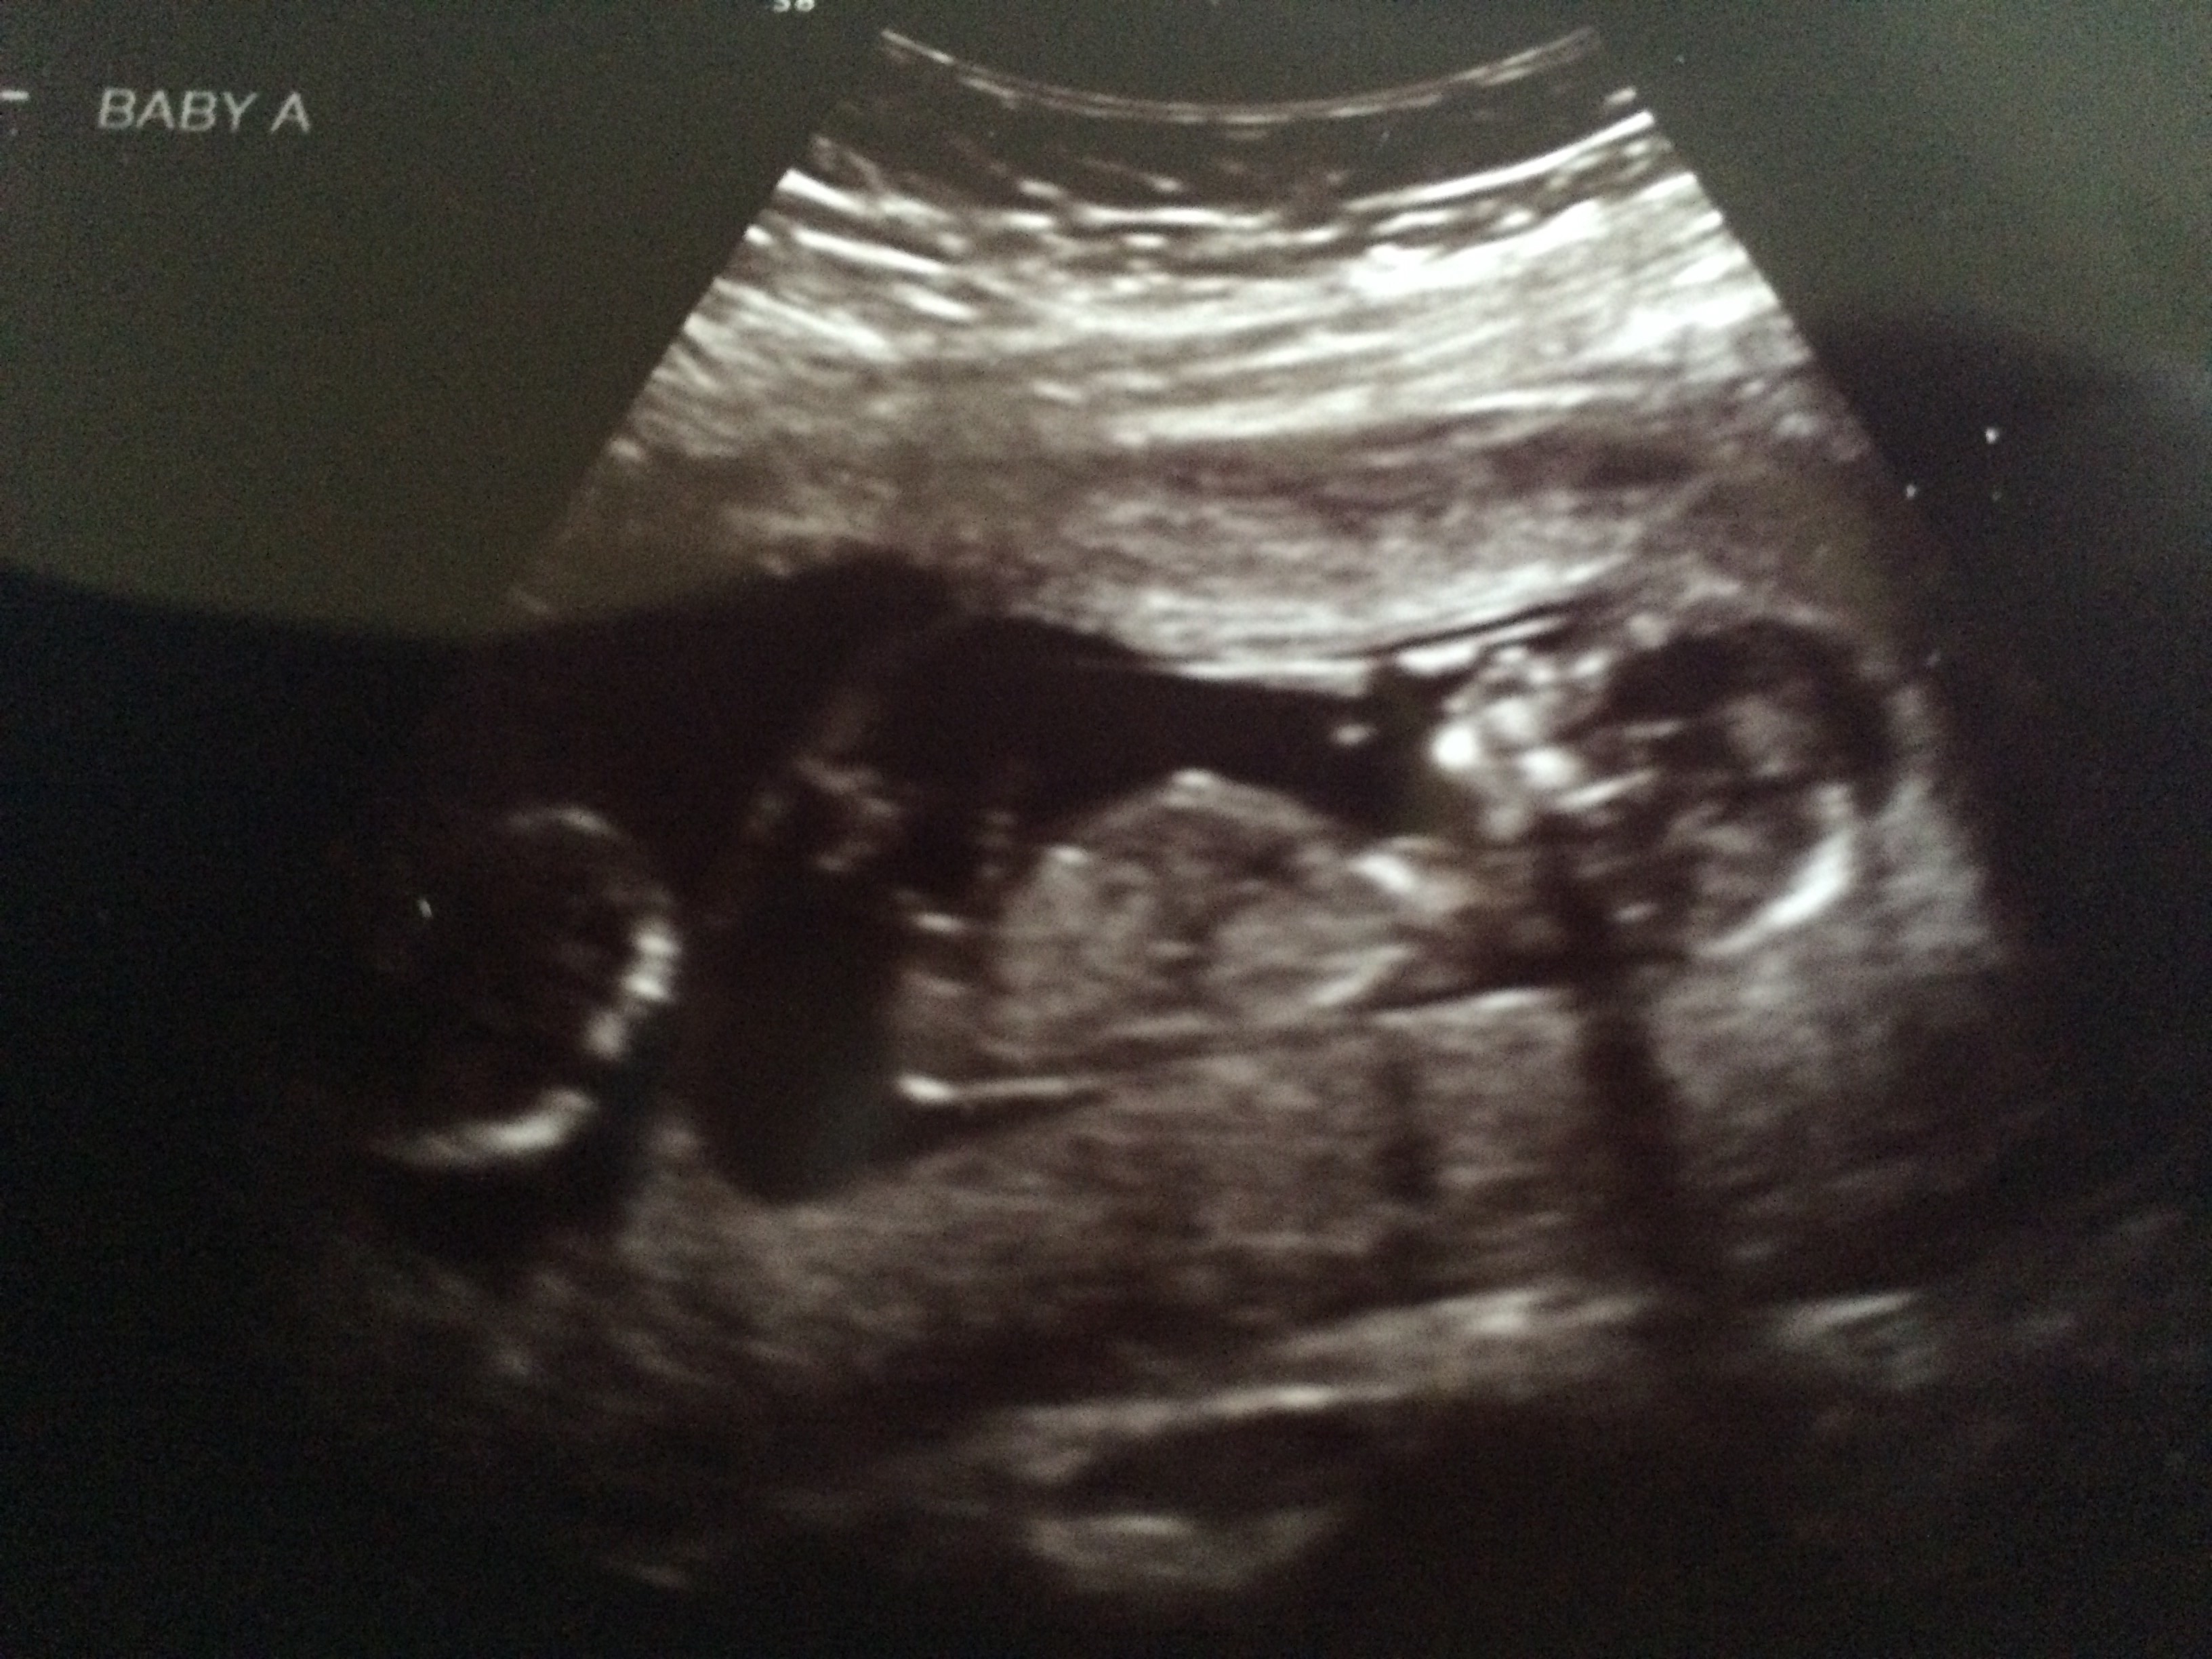

Here are my twins from my 13 week ultrasound. Both have strong heartbeats! One measuring at 13 weeks 4 days and the other 13 weeks 6 days. Tech made a guess and thinks they're boys!!